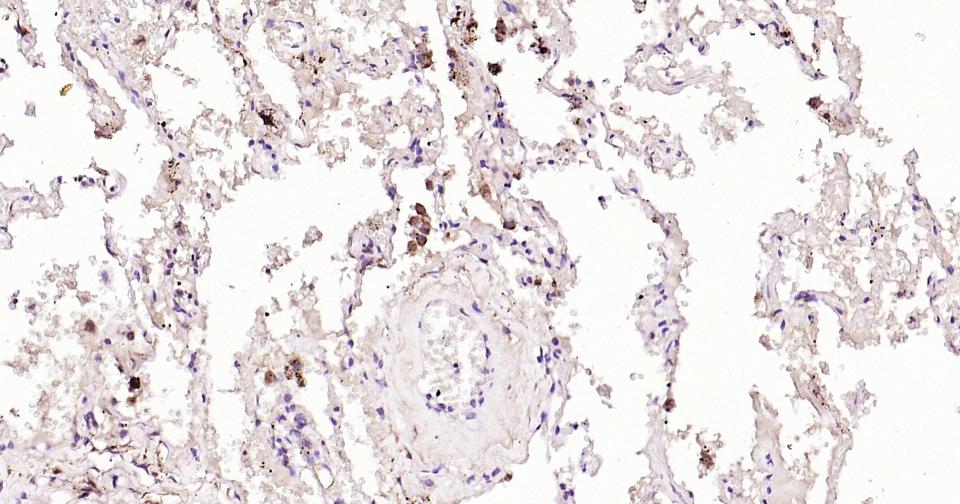

Paraformaldehyde-fixed, paraffin embedded Human Lung; Antigen retrieval by boiling in sodium citrate buffer (pH6.0) for 15 min; Antibody incubation with CCR-2 Monoclonal Antibody, Unconjugated(bsm-62473R) at 1:200 overnight at 4°C, followed by conjugation to the bs-0295G-HRP and DAB (C-0010) staining.